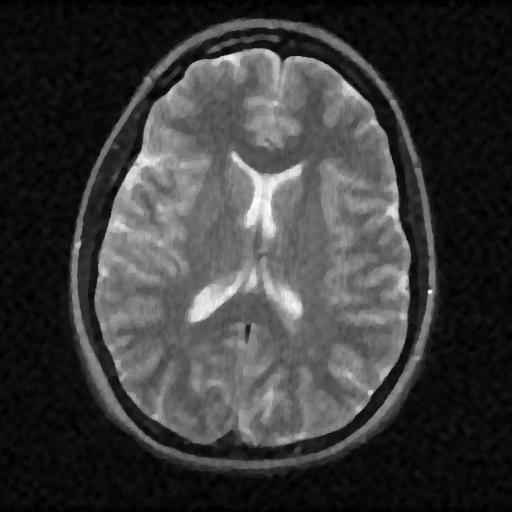

6.3. MR Image reconstruction

The second imaging application is concerned with medical imaging. Following the ideas from [32, 34], we simulate a multi-channel MRI sensing set-up, first using the same sine waves as in the previous experiment (results displayed in Fig 10), and then using spherical beam pattern (see in Fig. 11 for the results). We generate the classical Shep-Logan phantom, and set its dimension to .

The first experiment, depicted in Fig. 10 shows the results obtained by our method when using a Daubechies 4 sparsifying dictionary. Our results are compared to the single sensor analysis, and the results obtained by the Sum-of-Squares recovery [34, 32].

The recovery is obtained from noisy measurements, in which some additive Gaussian noise with variance has been added. The measurements are obtained by subsampling ( samples) of the Fourier transform. We see here that the fused compressed sensing is better capable of handling a multi-channel problem with unusual illumination (compared to the Sum-of-Squares method). Moreover, more details are preserved, when compared to the single sensor analysis method.

Some noise still appears in the image, but can easily be thresholded further if needed. One important aspect of MR Images that hasn’t been considered in this research, is the fact that they are sparse in gradient. One usually prefers to minimize the Total Variation instead of the norm or another frame using analysis.

Although we have not explicitly written the theory here, the recovered images in Fig. 11 show the results when using a TV minimization instead of the analysis.

The results were obtained from a spherical beam illuminating the input image. The measurements are obtained by sampling ( samples) of the Fourier coefficients at random iid from a Gaussian distribution. Again, some Gaussian noise with variance is added to every measurements.

| analysis | Sum of Square fusion | Fused analysis | Fused total variation | |

|---|---|---|---|---|

| SSIM | ||||

| PSNR | ||||

| error |

As presented in these examples, our method is capable of handling highly complex signals in potentially many dimensions yet keeping a very low number of samples taken. We can also empirically verify that the presented approach enjoys more robustness to noise and variations in scene illuminations than other known methods.